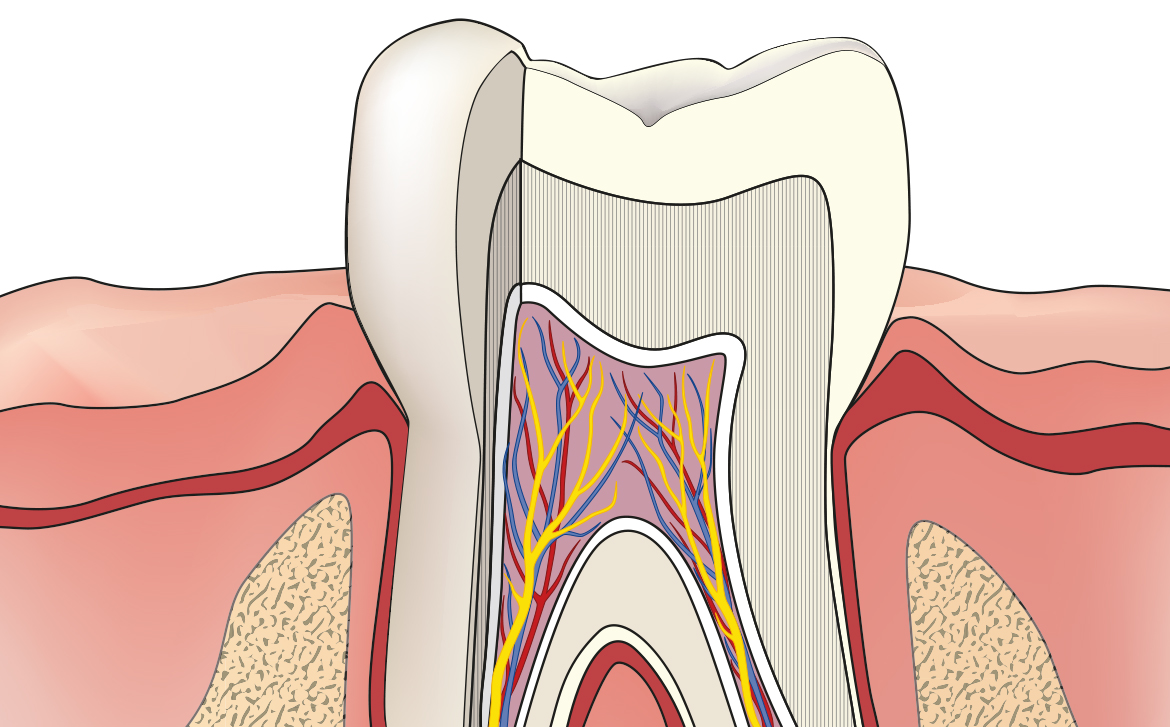

La polpa dentaria è un tessuto molto particolare dei nostri denti e altamente specializzato che negli adulti ha la funzione di percepire il caldo e il freddo principalemnte mentre nei bambin ha il compito di costituire la dentina. Nel caso in cui è presente una carie non curata con prontezza che arriva ad ingrandirsi ed estendersi fino a raggiungere proprio la polpa; il “canale” creatosi viene sfruttato dai batteri per arrivare nella zona interna del dente e causare danni irreversibili. E’ quindi inevitabile una cura endodontica che ha lo scopo di conservare il dente ed evitarne la sua estrazione.